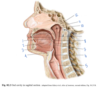

Which muscle is labeled by #1?

What is its action?

Aryepiglottic muscle

Pulls the epiglottis posteriorly to help close the larynx - opposes the thyroepiglottic muscle

(Restricts the opening like a purse string, but doesn’t close it completely)

Which structure is labeled by #7?

Hypoglossal nerve (CN XII)

- Inferior to the lingual and glossopharyngeal nerves

- Lingual from CN V3, labeled #2 here

- Glossopharyngeal CN IX, labled #4 here

Which muscle is labeled by #2?

What is its function?

Genioglossus

-

Protrude the tonuge

- The only muscle that protrudes the tongue!

- Deviate the tongue to the opposite side

- Depress the tongue

Which structure is labeled by #3?

Geniohyoid

Which muscle is labeled by #3?

What is its function?

Hyoglossus

Retract the tongue